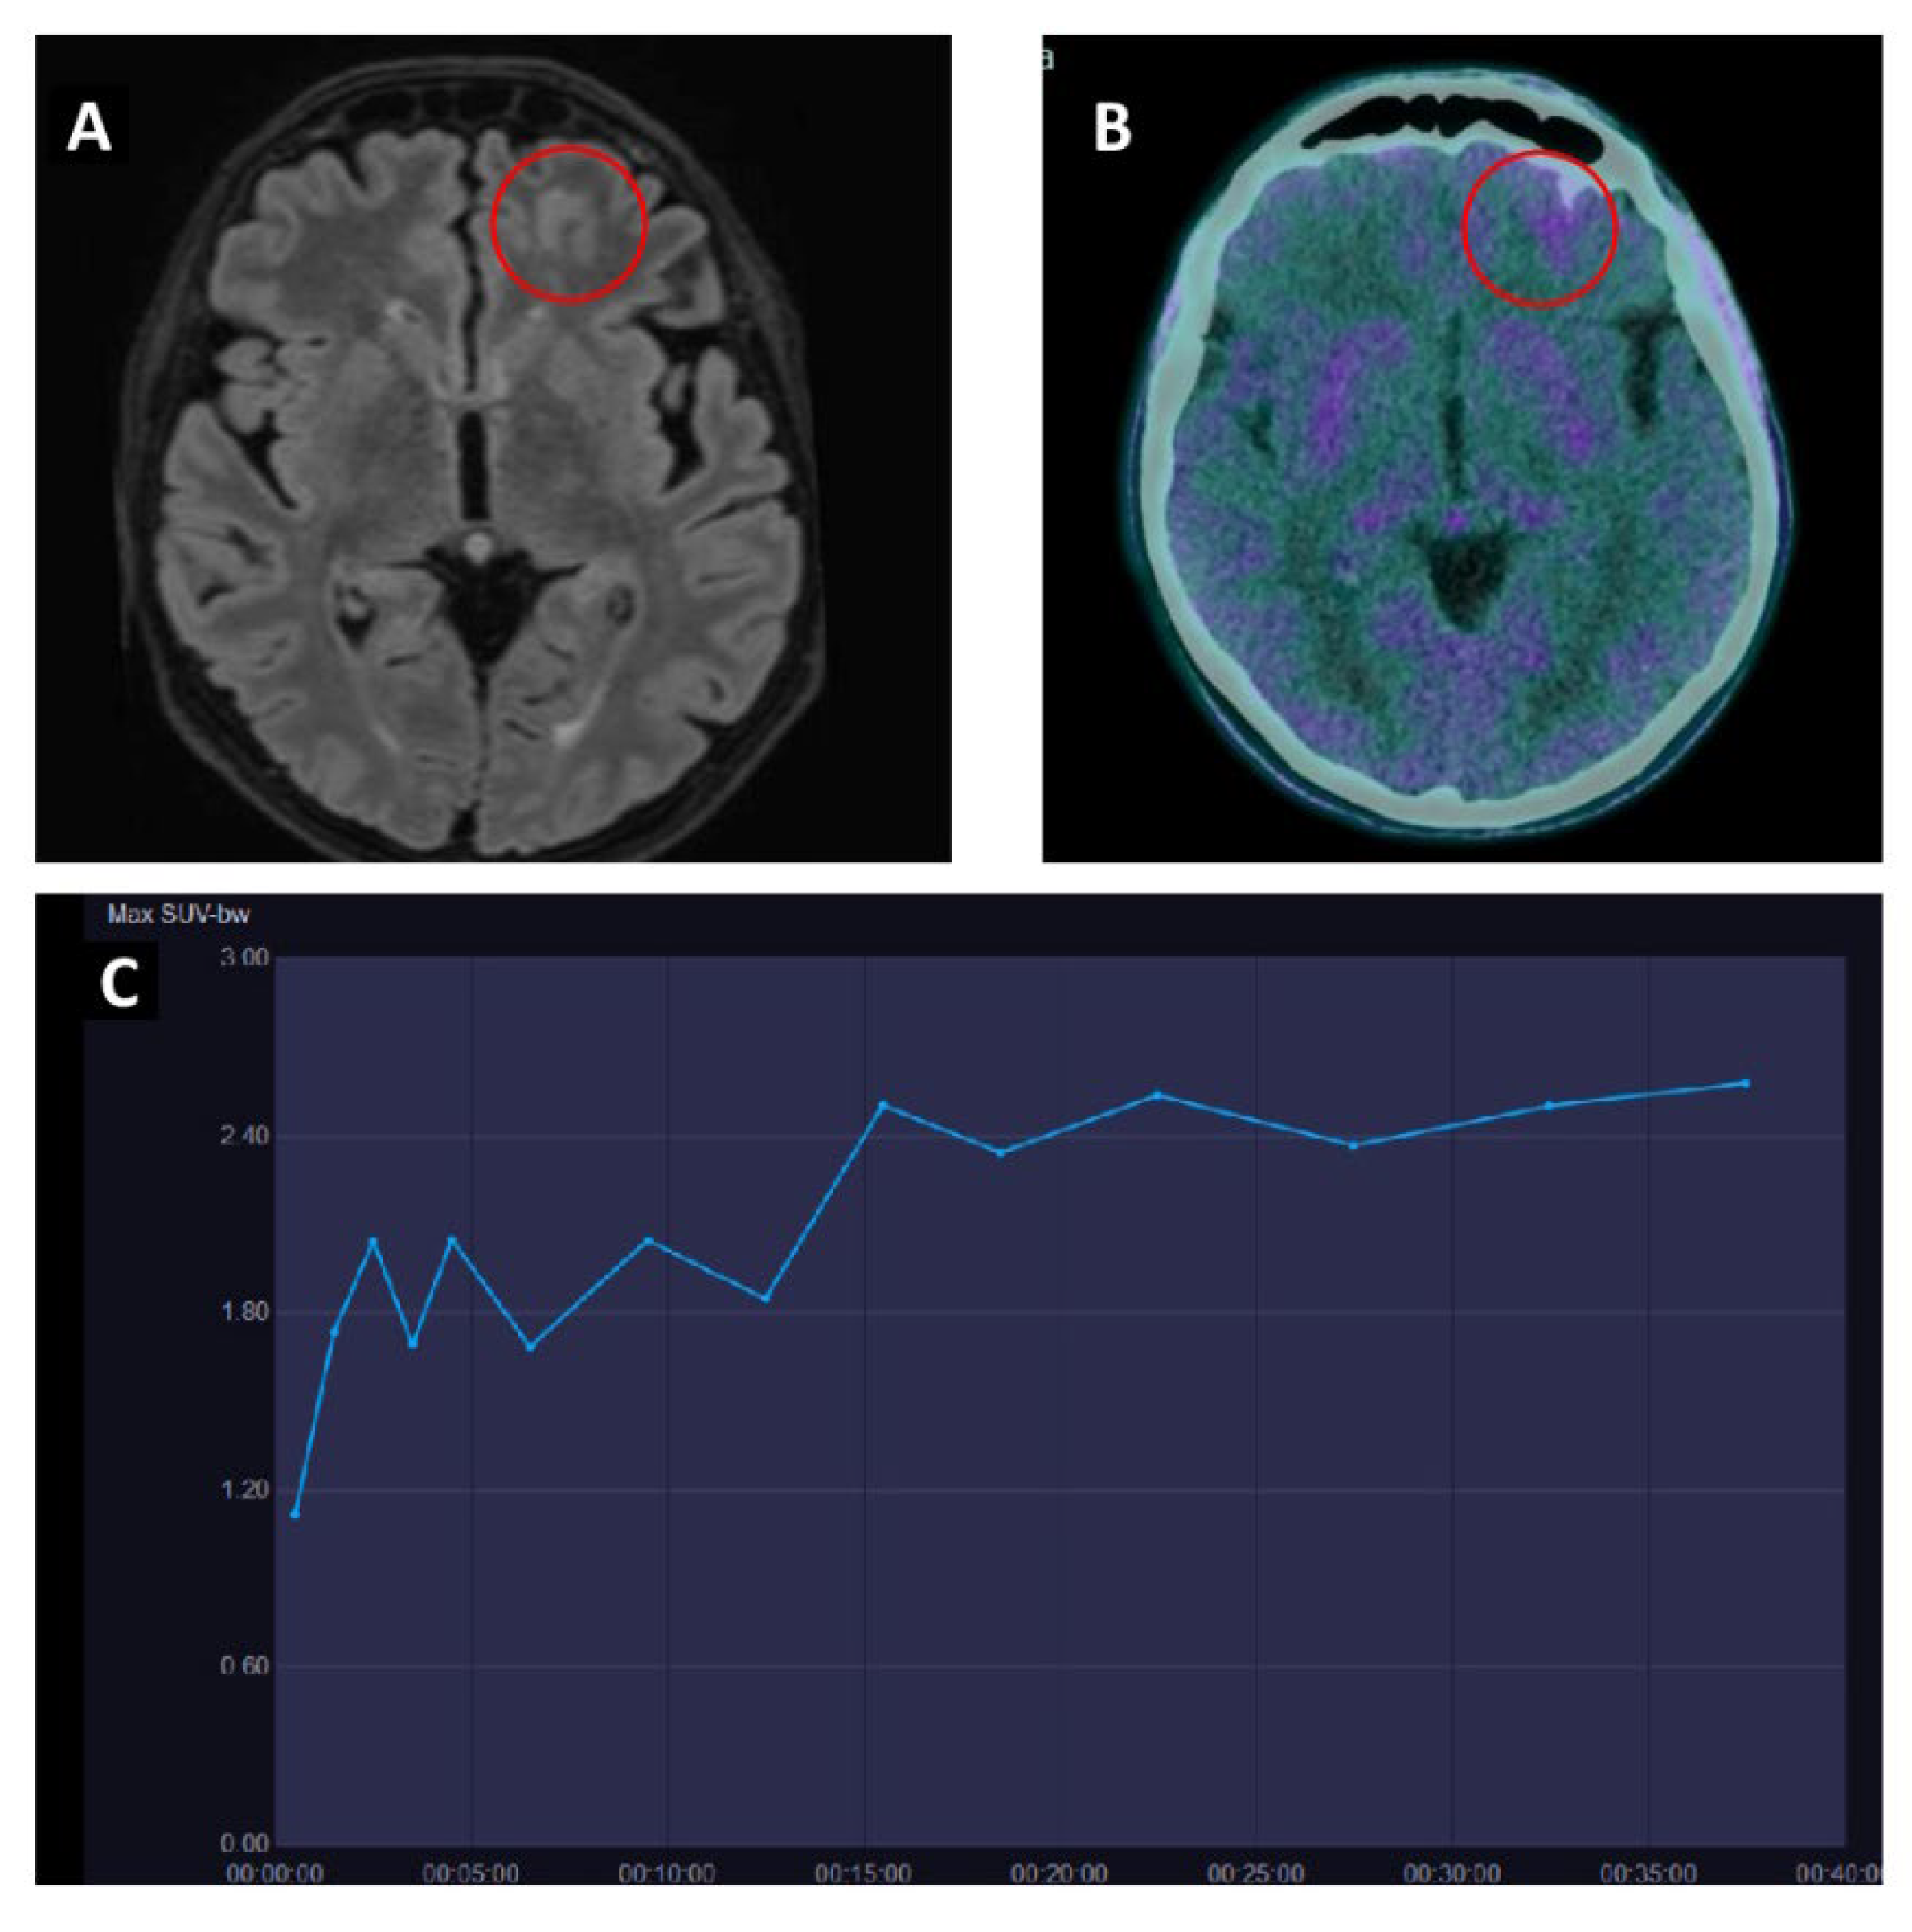

- Ceccon, G.; Lohmann, P.; Stoffels, G.; Judov, N.; Filss, C.P.; Rapp, M.; Bauer, E.; Hamisch, C.; Ruge, M.I.; Kocher, M.; et al. Dynamic O-(2-18F-Fluoroethyl)-L-Tyrosine Positron Emission Tomography Differentiates Brain Metastasis Recurrence from Radiation Injury after Radiotherapy. Neuro. Oncol. 2017, 19, 281–288. [Google Scholar] [CrossRef]

| Ceccon et al. [44] | 2017 | R | [18F]-FET | Solid neoplasms | 62 (14/48) | To role of dynamic PET scan to differentiate recurrence from radiation injury | TBRmean > 1.95 + a slope < 0.37 SUV/ h: accuracy 88% sensitivity 83% specificity 93% |

| Kebir et al. [45] | 2016 | R | [18F]-FET | melanoma | 5 (NR) | To evaluate pseudoprogression in patients treated with ICI | TBRmax was higher in patients with true progression (5.4 vs. 2.5), as well as time to peak was significantly shorter (17 min vs. 45 min) |